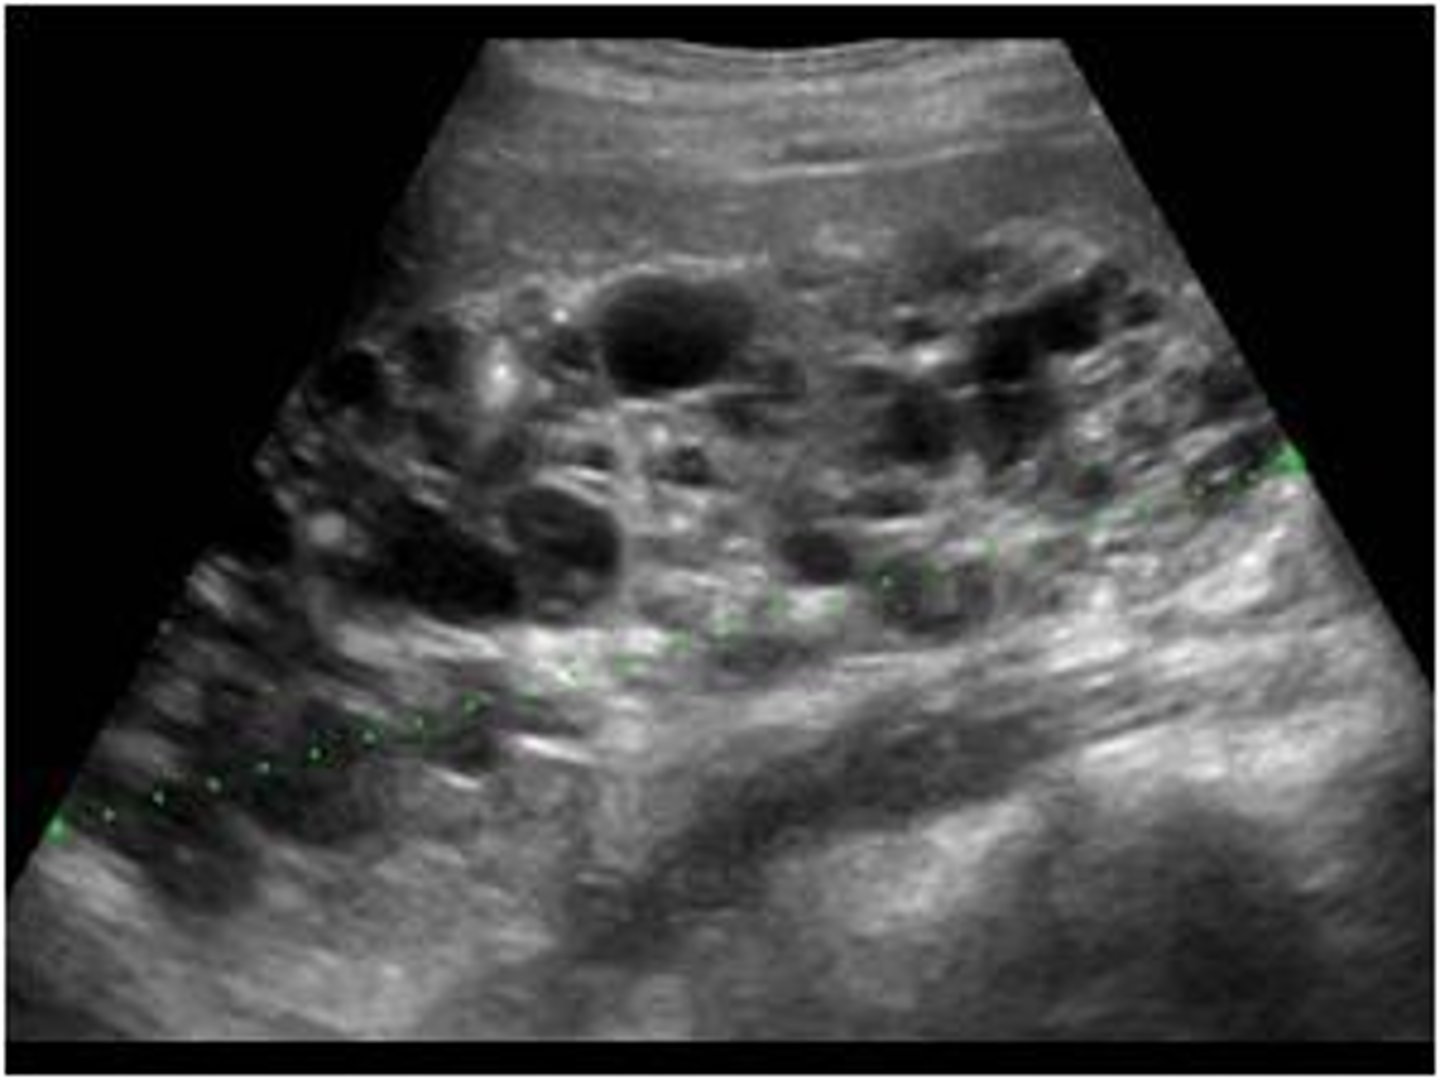

What is the best initial diagnostic test for autosomal dominant PCKD? What is the best overall?

Initial: renal US

Overall: MRI